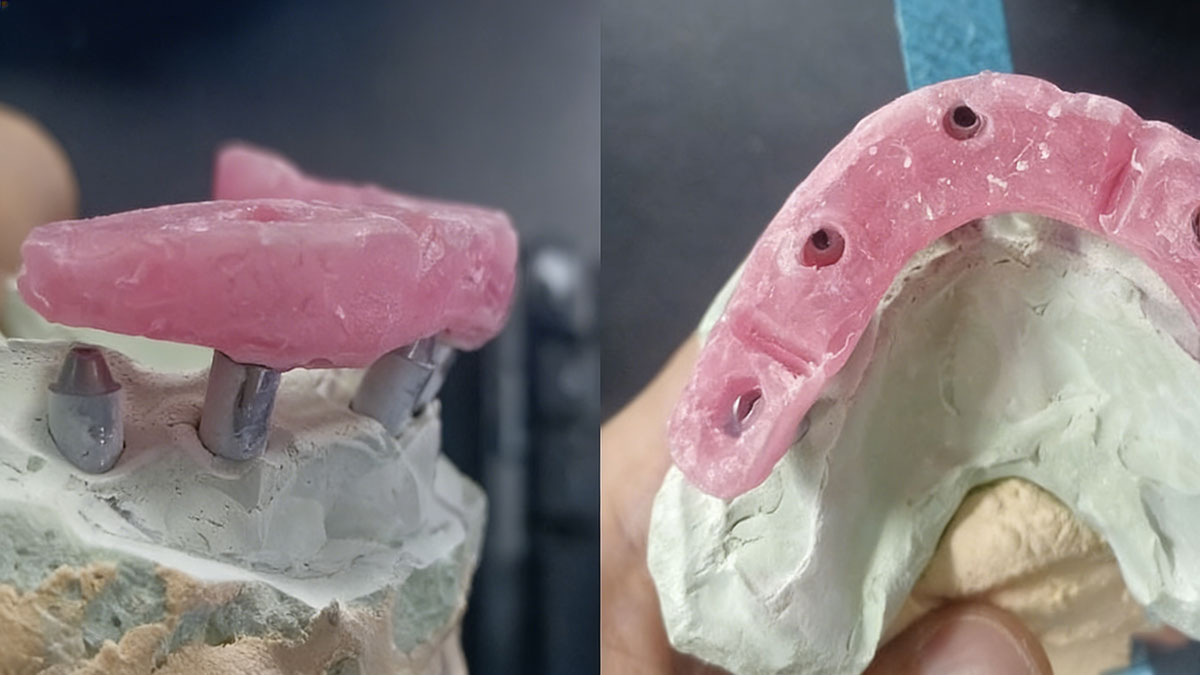

We recently received a request for full mouth dental implants. It was from a very experienced dentist. He shipped stone models to us, along with a bite registration. On the stone models and the bite registration, he also marked mid-line, and asked for design before production.

Normally, we would ask to mill an aluminum bar with 3D printed bridge to try fitting and bite. This was the common practice for big implant cases. However, the stone models and the bite seemed to be taken well, and mid-line was well marked. So the doctor asked to directly mill a titanium bar with temporary bridges.

About 5 days later, we received stone models, the titanium bars, temporary bridges, and a new bite registration. With the help of pictures and new bite registration from our doctor, we re-designed titanium bars and temporary bridges.